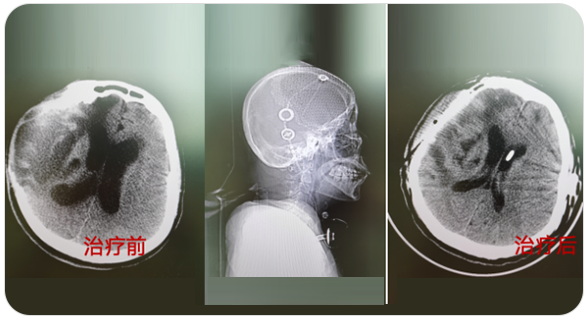

从事神经外科工作30年,擅长脑与脊髓血管类疾病、肿瘤、外伤等疾病的诊断与治疗,尤其擅长神经介入治疗各类脑血管疾病。累计完成介入栓塞颅内动脉瘤2000多例,颅内血管畸形数百例,夹闭颅内动脉瘤数百例,手术颅内与脊髓肿瘤数百例。在脑和脊髓血管病、肿瘤、外伤等方面有丰富的经验和较深造诣。

精通颅内动脉瘤介入栓塞和手术夹闭双技术,系统掌握脑动静脉畸形、颈内动脉海绵窦漏、硬脑膜动静脉漏等颅内血管疾病的诊疗和手术,精通颈动脉、椎动脉狭窄的血管内重建技术,以及颈动脉狭窄的内膜剥脱手术技术。在颅内肿瘤、椎管内肿瘤、颅脑损伤、高血压脑出血等疾病的诊治和手术,脑功能性疾病立体定向手术治疗等方面也积累了丰富的经验。